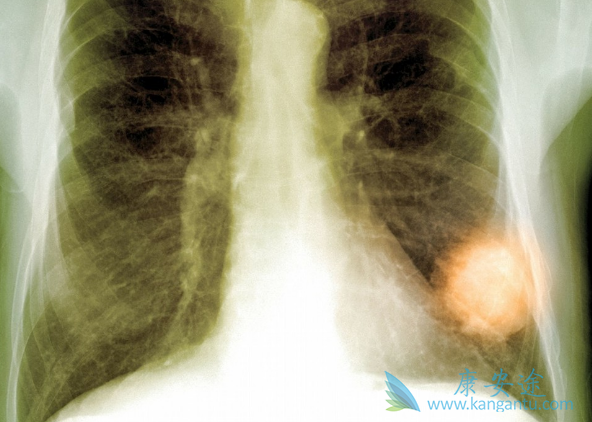

从价格上来看,英国阿斯利康的原研药Tagrisso一个月费用为12750美元(约合87600人民币),而奥希替尼 Osicent是中国的肺癌患者可以负担的治疗方案。仿制药奥希替尼(Osicent)不但效果好,安全性也更好:使用一代EGFR抑制剂治疗非小细胞肺癌的有 44.8%的人曾出现≥3级(比较严重)的不良反应,有18.1%因此中止治疗;相比之下,使用奥希替尼的患者只有 33.7% 曾出现≥3级的不良反应,有 13.3% 中止治疗。